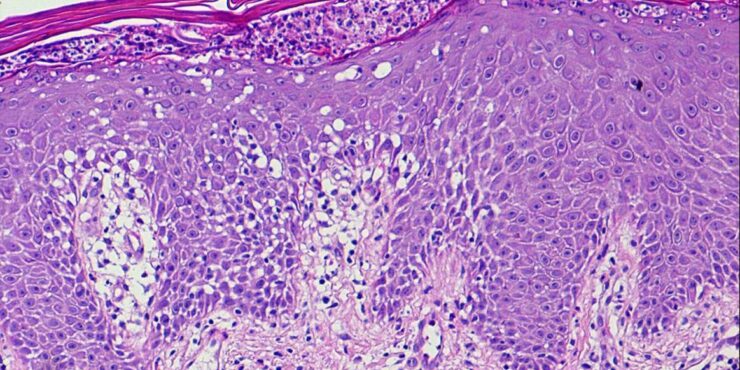

Erythema elevatum diutinum = الحمامى المرتفعة الدائمة Erythema Elevatum Diutinum This rare condition is characterized by persistent, initially red to violaceous and later brown to yellow papules, nodules, and plaques . The lesions, typically distributed symmetrically on the extensor surfaces of the extremities, are initially soft and then evolve into fibrous nodules. Histopathologic Features. In […]